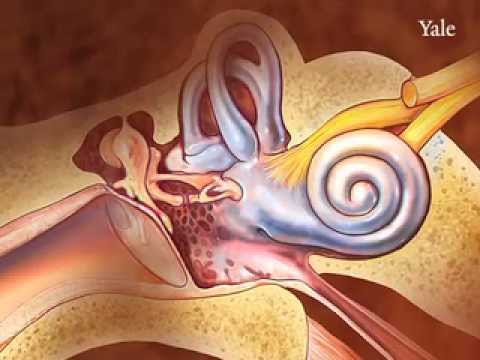

Why do mitochondrial diseases often affect very specific tissues, such as cells in the inner ear? Ge [...]